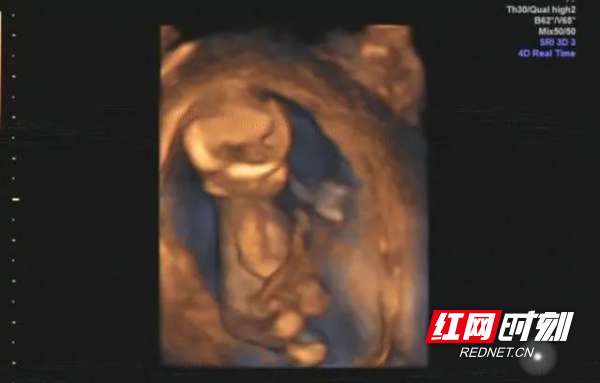

四维NT检查中的胎宝图像。

NT检查即颈项透明带检测,主要是通过B超方式检测胎儿颈项部透明带的厚度,有助于早期发现宝宝的染色体疾病,是评估胎儿早期唐氏综合征风险的一种检查。

NT检查是胎宝孕早期的重要排畸检查,筛查时间非常严格。检查时间通常在孕11-13周+6天。不能在小于11周或者大于14周时检测,因为小于11周时,胎儿还没有全部成型,此时检测不到,大于14周以后,颈项部皮下的淋巴管已经形成,对透明带的测量也会有影响。

颈项透明带的厚度也有一个正常的参考范围,NT值<2.5mm 正常;NT值≥2.5mm 则考虑胎儿是否存在结构的异常或者染色体的异常,咨询医生是否需要做进一步检查,或做羊水穿刺诊断。

一般来说,NT增厚,预示着胎儿存在异常风险,NT值越大,则存在异常的风险就越大。